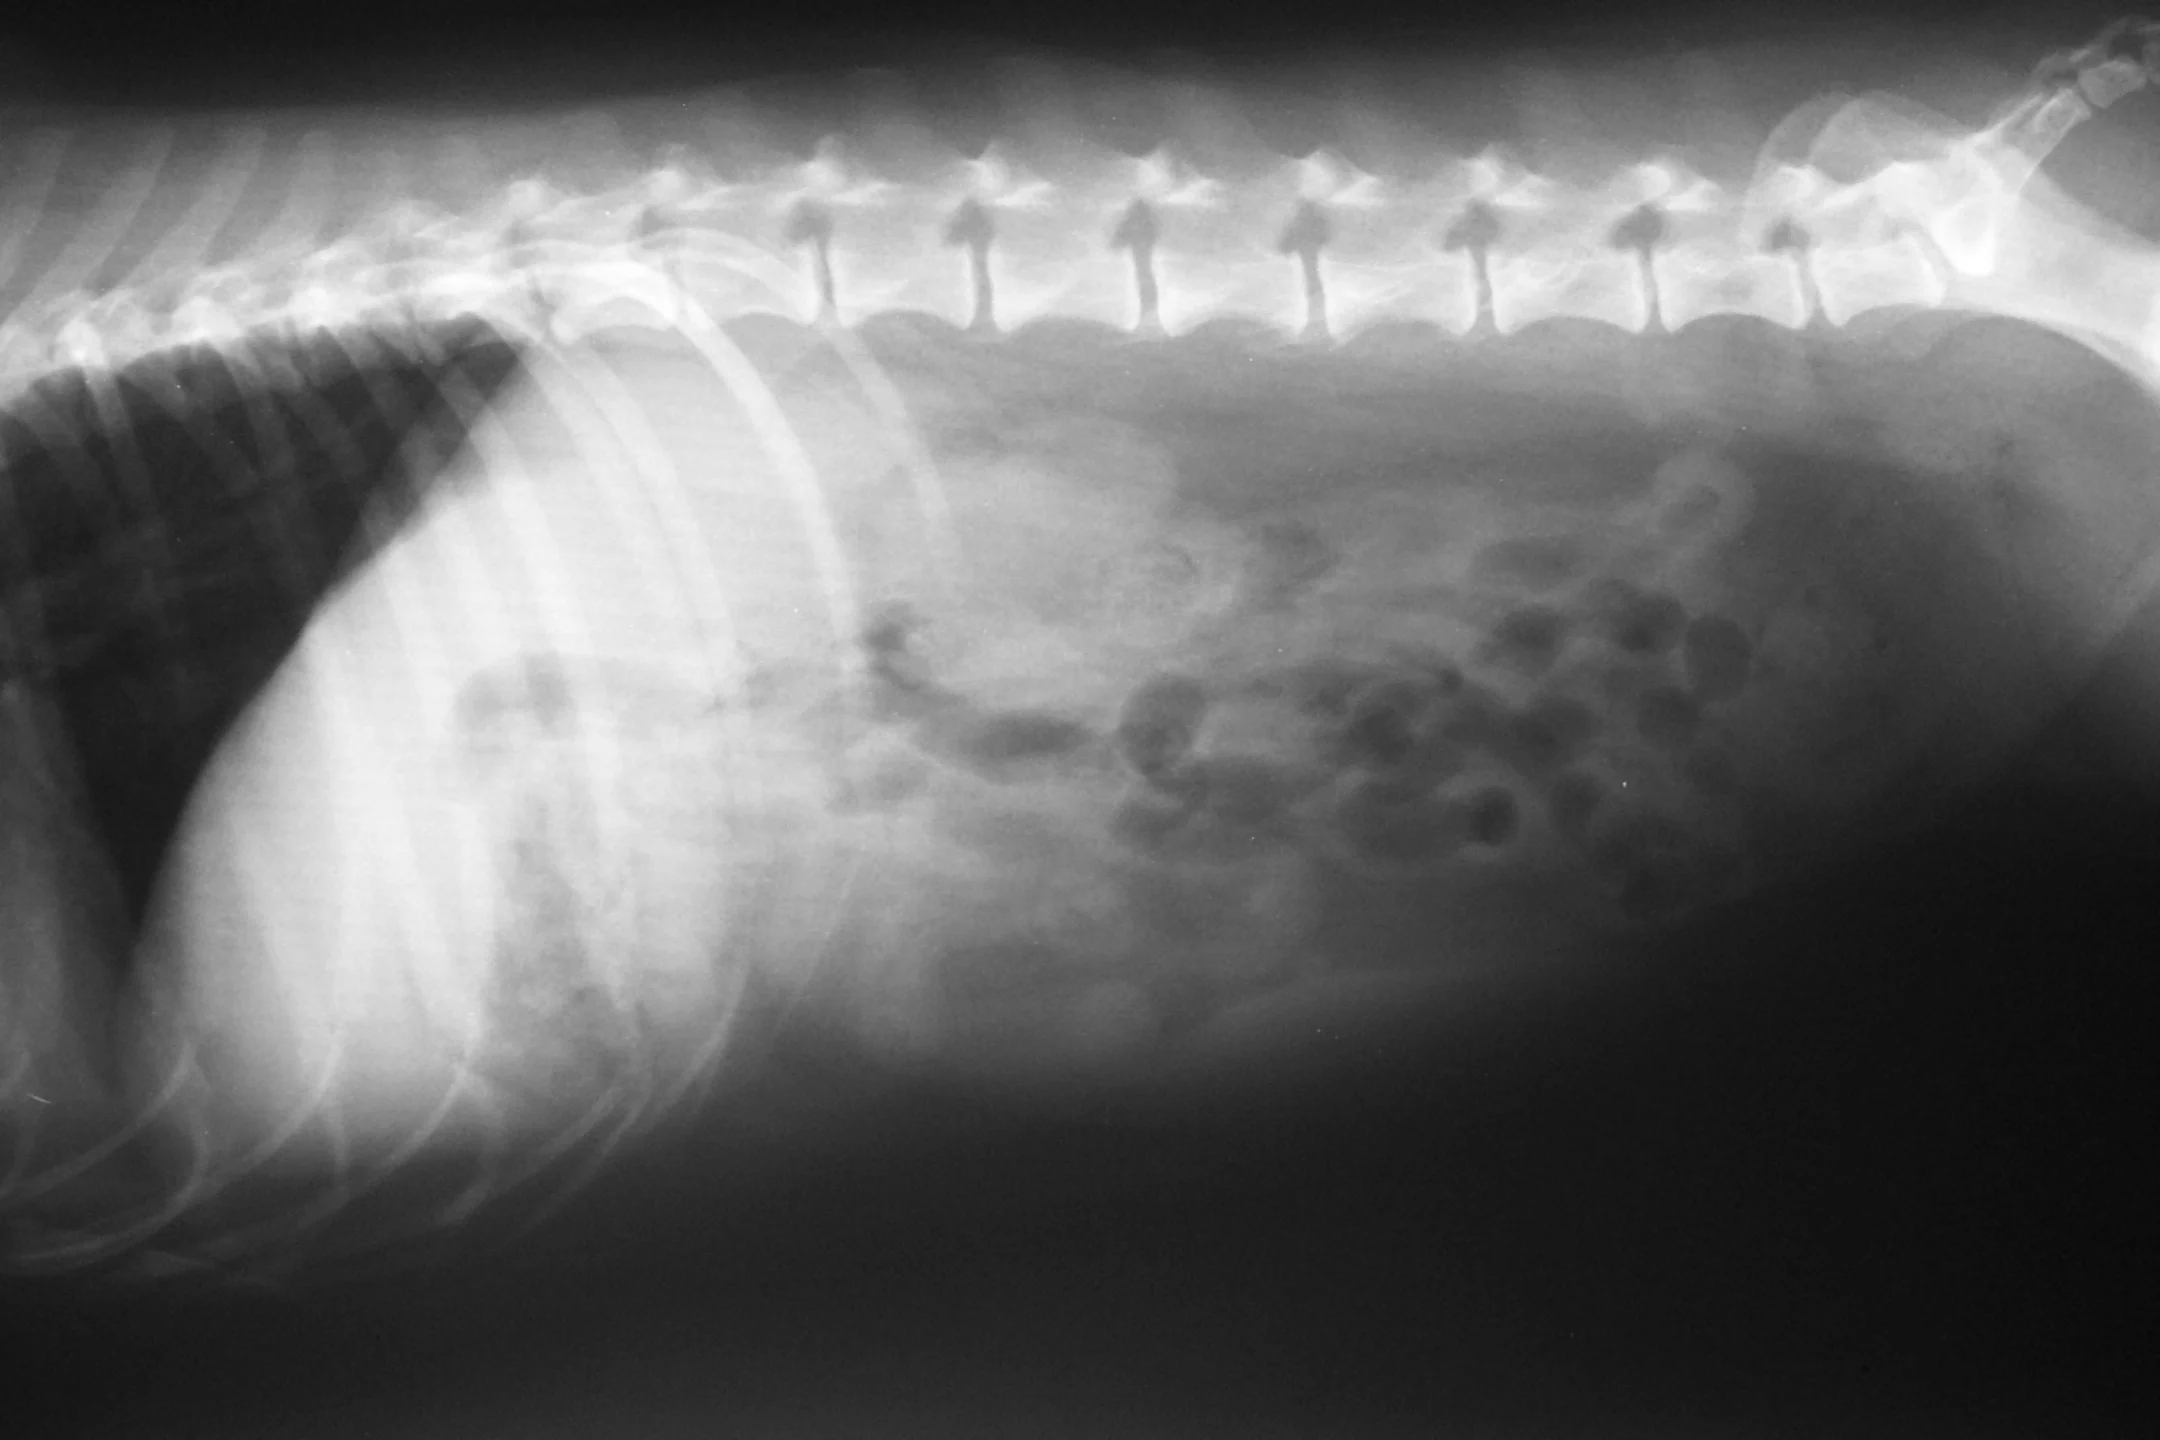

Recent diagnostics included abdominal radiographs (Figure 1) and trial therapy with metoclopramide (5 mg PO Q 8 H) for the vomiting and sulfasalazine (125 mg Q 8 H) for the diarrhea. Neither treatment resulted in any significant improvement.

Lateral and ventral dorsal abdominal radiographs

What is your interpretation of the radiographs in Figure 1?

Abdominal serosal detail is adequate. There is no evidence of radiopaque gastrointestinal foreign bodies or intestinal obstruction. The remaining abdominal and extraabdominal structures are within normal limits.